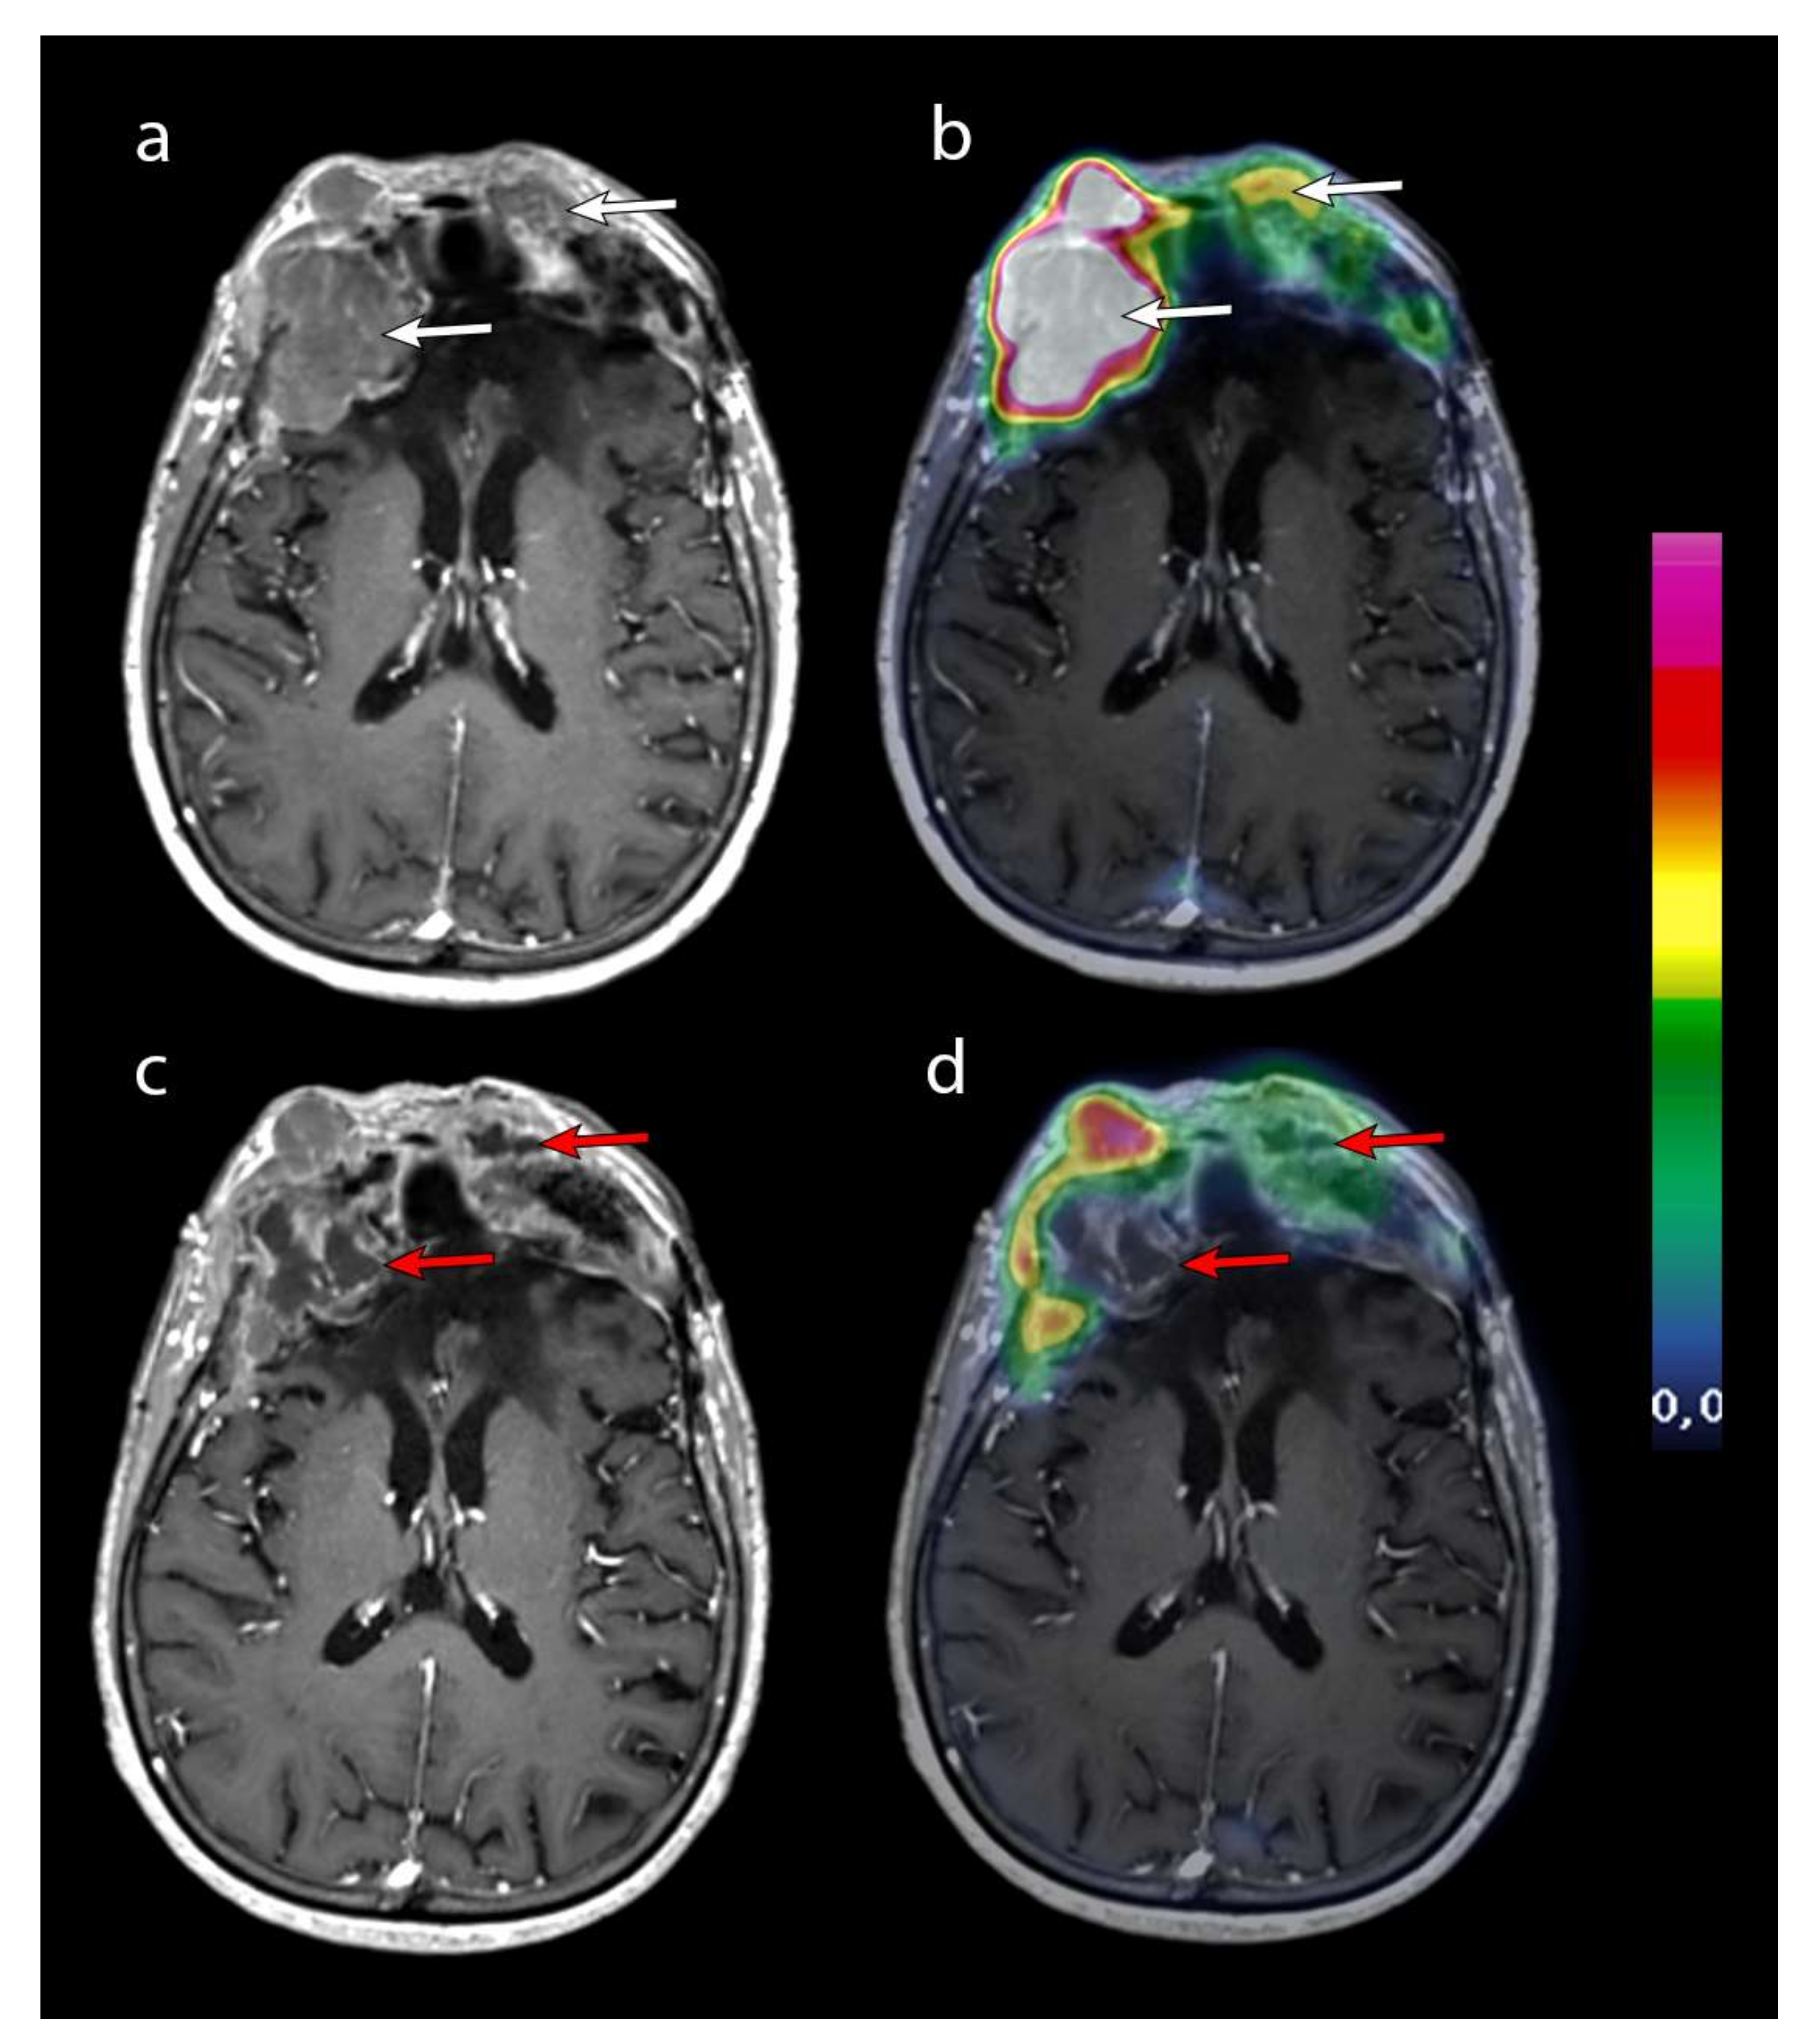

| 1 | 3 | II | 7.4 | 10.6 | PD | 2 months |

| 2 | 3 | II | 26.3 | 29.6 | SD | 10 months |

| 3 | 3 | II | 45 | 29.6 | SD | 17 months |

| 4 | 2 | II | 14.5 | 29.6 | SD | 16 months |

| 5 | 2 | III; II | 12.3 | 29.6 | SD | not reached at 12 months |

| 6 | 3 | II | 16 | 29.6 | SD | not reached at 9 months |

| 7 | 3 | II | 16.8 | 29.6 | SD | N/A * |

| 8 | 3 | II | 15.4 | 29.6 | SD | not reached at 16 months |